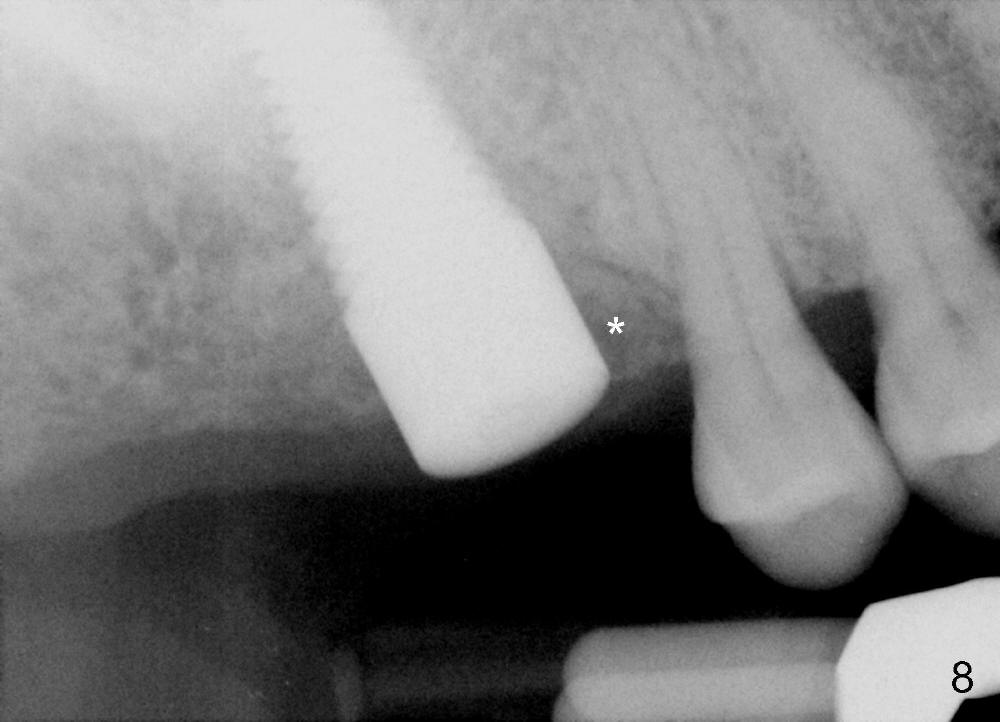

The upper right 1st molar fractures, the lingual portion mobile (Fig.1). There are deep pockets mesiolingually and distolingually. Fig.2 is preop PA, showing mesial bone resorption (*). The 84-year-old lady agrees extraction and immediate implant. Extraction is difficult due to not only root fracture but also hemorrhage. Following debridement of granulation tissue, the 3 sockets are packed with gauze for hemostasis. Even so, there is oozing from the bone. The septum can not be seen clearly. Its position is determined by an explorer. Osteotomes have to be used for osteotomy in the septum, followed by taps. The first intraop PA shows that 5x20 mm tap penetrates the sinus floor (Fig.3 ^). The osteotomy is further enlarged until 7x17 mm tap with stability (Fig.4). So far there has been no sign of sinus membrane perforation. Mixture of freeze dry mineralized bone and Osteogen is placed in the socket and pushed to the buccal and lingual walls as well as into sinus using a 4 mm flat end osteotome. A 7x17 mm implant is initially difficult to be inserted possibly due to blockage by bone graft. The osteotomy have to be recreated by a series of osteotomes and taps before placement of the 7x17 mm implant. It appears that the apical threads have been engaged into the sinus floor for primary stability (Fig.5). The insertion torque is 40 Ncm. According to our experience (1,2), this is not enough; finally the torque is increased to 60 Ncm by turning the implant more apically. The large implant obliterates the socket mesiodistally; the buccal and lingual gaps are filled with bone graft, followed by a collagen membrane (Fig.6 *) and suture. In order to protect the membrane, a short abutment is placed (A) and perio dressing (Fig.7*) is placed without occlusal interference. The abutment is removed 1 month postop, as the perio dressing has been dislodged. The patient returns for restoration 8 month postop. Bone regeneration occurs apparently in the coronal aspect of the implant (Fig.8), especially mesially (*, as compared to Fig.5). The gingiva-level implant is slightly subgingival mesially (Fig.9 M), probably due to high placement (compare to Fig.6). There is no bone resorption 6 months post crown (Fig.10 C) cementation.